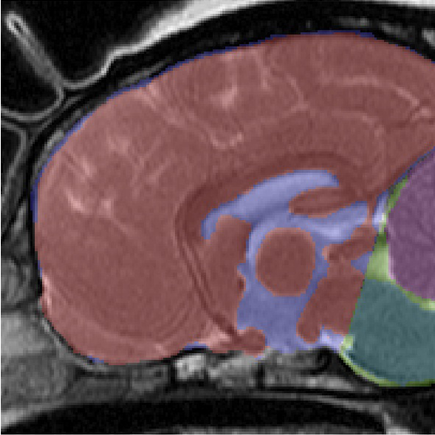

In an

April 2012 study by

Thomas A. Shaw, Imelda M. McGonnell, Colin

J. Driver, Clare Rusbridge, and Holger A. Volk, they

concluded that:

"the CKCS has a relatively larger cerebellum [in purple at right] than small breed dogs and Labradors and there is an association between increased cerebellar volume and SM in CKCS. In contrast to small breed dogs and Labradors, CKCS exhibit correlation between increased cerebellar volume and cerebellar crowding within the caudal CCF, suggesting that CCF growth in CKCS is not keeping pace with the growth of the cerebellum.

"These findings support the hypothesis that it is a multifactorial disease process governed by increased cerebellar volume and failure of the CCF to reach a commensurate size."